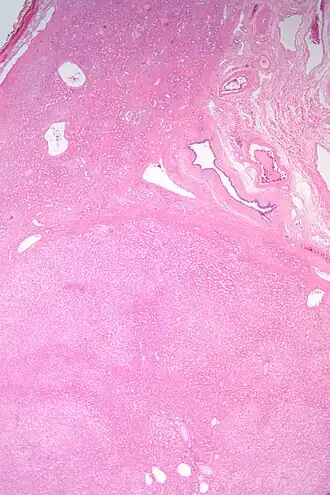

| Adenoma hepático (parte inferior da imagem). H&E | |

Adenoma hepático ou Adenoma hepatocelular é um tumor benigno hepático associado a níveis elevados de estrógeno. Mais frequentes em mulheres em idade fértil que usam contraceptivos orais. Geralmente são descobertos incidentalmente por razões não relacionadas, com diâmetro de 8 a 10 cm, enquanto não causam sintomas. Se não for tratado há um risco de 30% de hemorragia, portanto recomenda-se ressecação cirúrgica.